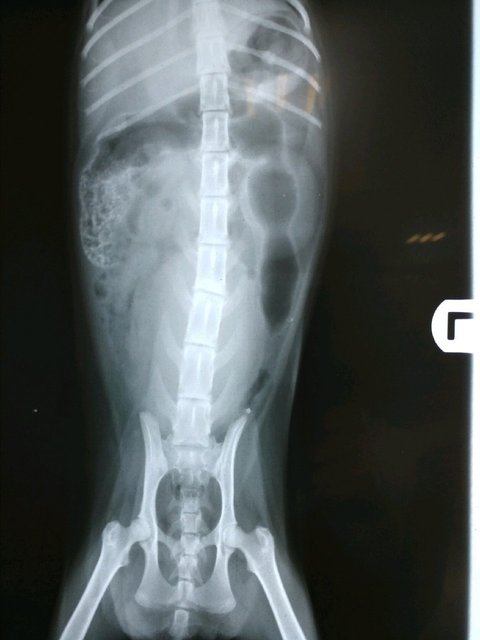

척추쪽 검사 모습 (요추4번에 문제)

첫번째 데려갔던 병원은 수술이 안되어, 급히 다른 병원을 찾아 검사를 해보니, 척추에 신경이 눌려 배뇨를 못하는 상황이었고.. 혈뇨가 더 쌓이면 당장 죽을 수도 있다는 말에 주말에 여는 병원이 없어 더 알아 보지도 못하고 덜컥 입원을 시켰습니다. 카데터를 꽂아 혈뇨가 배출되게끔 하고, 주사처리로 악화된 수치들을 낮춘다는 처치들을 하나 둘 추가하다 보니, 최소한의 처치를 했는데도 금액이 정말 눈더미처럼 불어나더군요..(이틀동안, 현재까지 정확히 59만4천5백원이라는 비용이 들었습니다.)

상태는 더 자세한 검사를 해봐야 알겠지만, 척추 수술을 못하면 카데터로 상황이 좋아져도 평생 자연 배뇨를 못하고 강제 배뇨를 해야 한다고 합니다. 하지만 혈뇨만 잡으면 세균성이 아닌 이상, 척추 문제가 생명엔 지장이 없고, 배뇨만 도와주면 건강히 살수도 있다고 하셨습니다